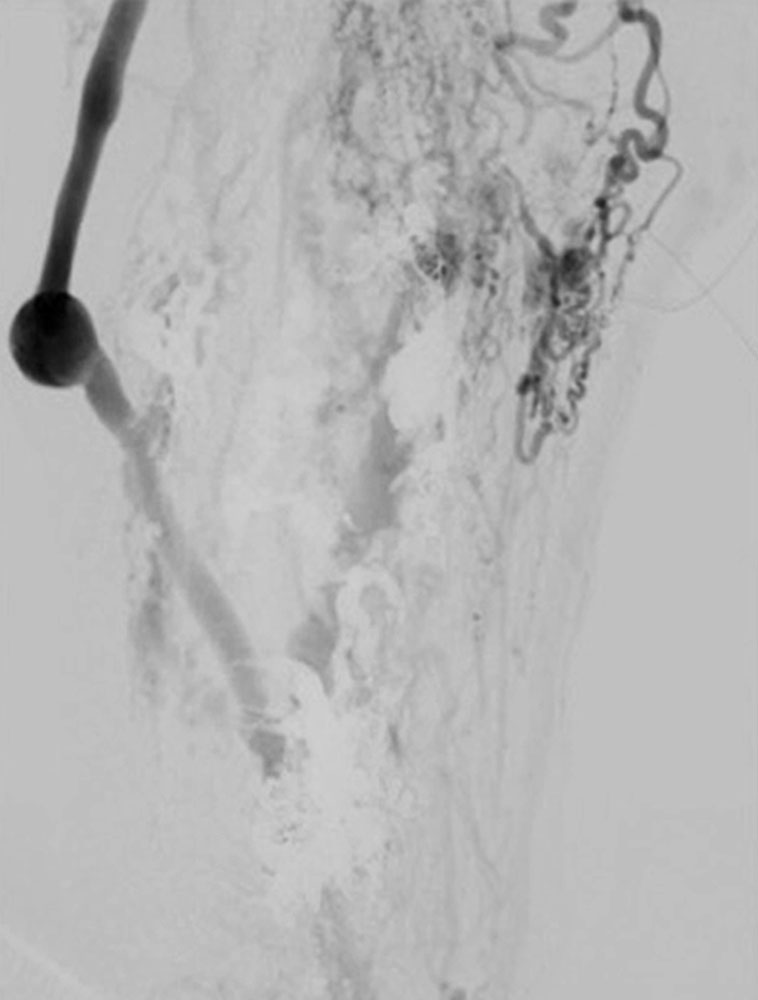

Es ist nur bei kleinen, sehr lokalisierten Prozessen in seltenen Fällen möglich, eine ausreichende primäre Radikalität zu erreichen. Meist werden diese Eingriffe dann mehrzeitig oder in Kombination mit anderen Verfahren durchgeführt (z. B. zusätzliche Sklerosierung oder Embolisation).

Bei arteriovenösen Malformationen hat sich die Technik der Skelettierung der Gefäße mit Unterbindung von zuführenden Fistelästen nicht bewährt, da sich häufig über Kollateralverbindungen eine identische Füllung und Hämodynamik ergeben kann.

Inzwischen werden resezierende Verfahren an den Gefäßen üblicherweise erst nach oder in Kombination mit endovaskulären Techniken eingesetzt.